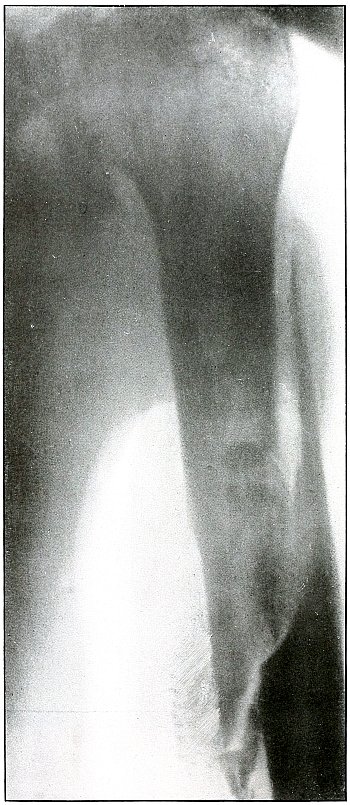

Gunshot fracture, femur |

114 |

| 53. |

Gunshot fracture, femur |

116 |

| 54. |

Gunshot fracture, femur |

118 |

| 55. |

Gunshot fracture, femur |

120 |

| 56. |

Gunshot fracture, femur |

122 |

| 57. |

Gunshot fracture, femur |

124 |

| 58. |

Gunshot fracture, femur |

126 |